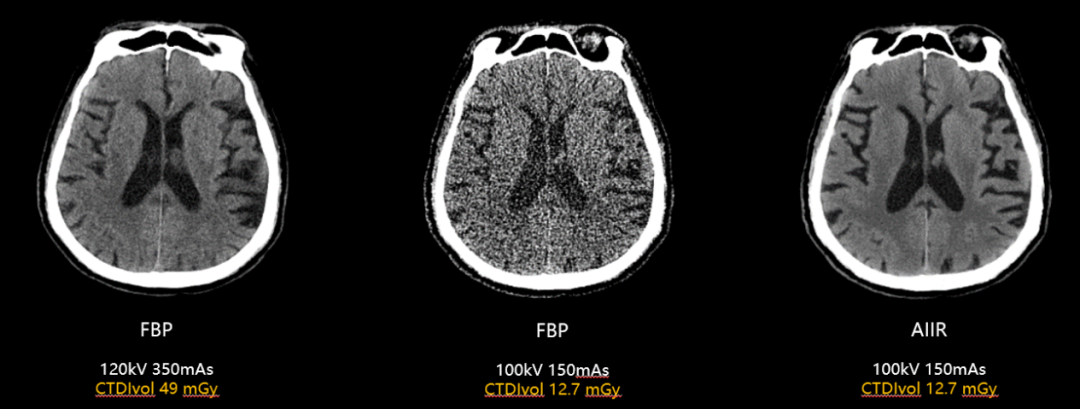

业内首款第5代CT图像重建的超高端CT:

搭载双精度图像感知AIIR技术,融合AI深度学习与全模型重建,实现超低剂量下的强降噪能力(噪声降低最高达98%),密度分辨率提升267%、空间分辨率提升150%,对宽体的锥束伪影、其他原因导致的条状伪影都起到极佳的消除能力,为低剂量成像提供创新解决方案,让检查更安全,为疾病的防、诊、治起到更大作用。